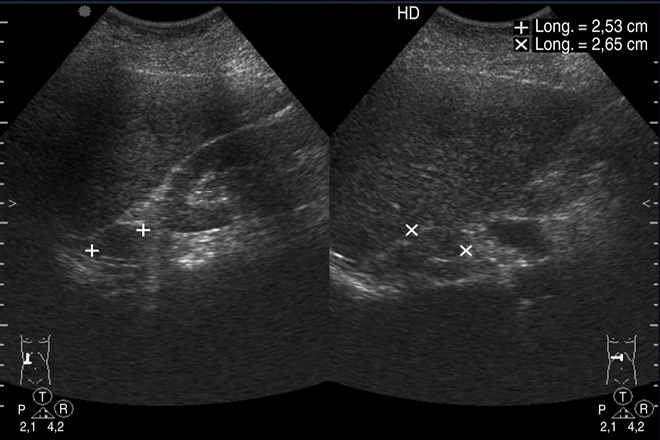

El diagnóstico se basa en la historia clínica, el examen físico y los hallazgos en los estudios de imagen. Los estudios de elección son la ecografía y la tomografía abdominal, que brindan información sobre la morfología, composición, localización y relación con órganos vecinos. Los quistes esplénicos no provocan alteraciones en los análisis de laboratorio.

Se sugiere un seguimiento con ecografía cada tres meses después de la cirugía para descartar recurrencia del quiste y medición de Ca 19-9, tres meses después de la cirugía para descartar la recurrencia del quiste epidermoide congénito.